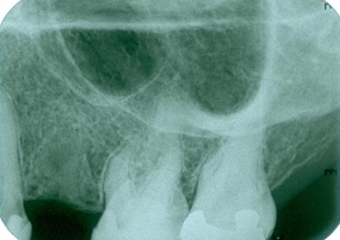

Imagem após extração do dente comprometido